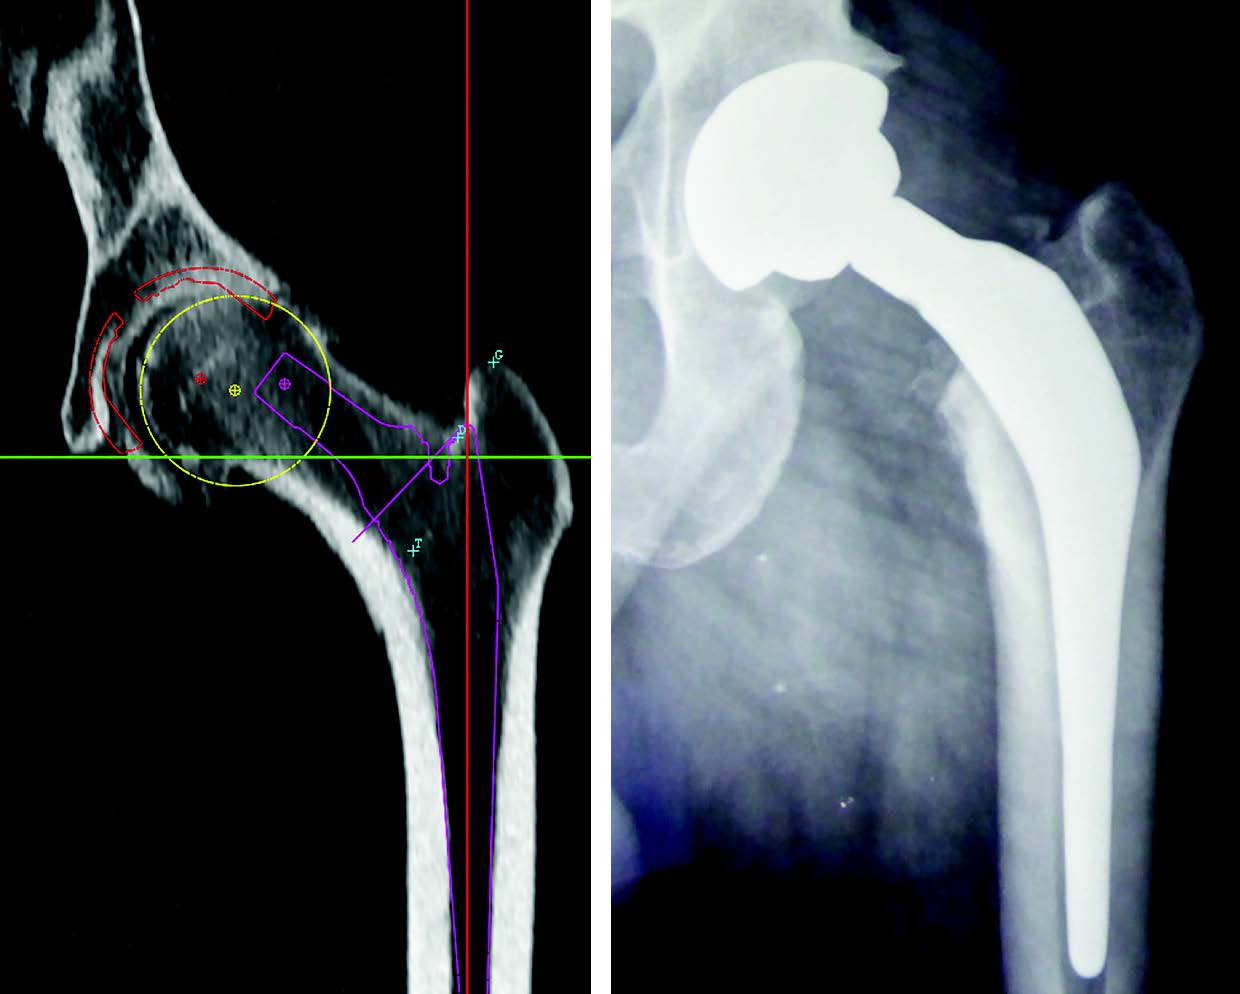

Step 3: The position of the pelvis uses the Lewinnek plan (reference plane based on the anterior superior iliac spines and the pubic symphysis). It is calculated automatically by the software. It can be used to quantify acetabular inclination and anteversion (Fig. 3).

Step 4: acetabular planning: 3D acquisition is used to measure the native acetabulum and to select the position of the acetabulum (Fig. 4).

Step 5: femur position: the software measures the posterior bicondylar line then defines a femur from the front and side on (Fig. 5). The greater trochanter, the digital fossa and the lesser trochanter landmarks can thus be specified. All of these measures are used to define the femoral torsion and offset.

Step 6: femoral stem planning: we can position a stem, choose the size, evaluate bone stress, measure bone resection (that we can compare during surgery using the callipers) and choose the ball (Fig. 6 and 7). The software calculates lengthening and offset depending on the implants selected.

In my experience (prospective study on 100 consecutive records) the accuracy of acetabulum size CT planning is remarkable, with an agreement rate between the planned acetabulum and the implanted acetabulum of 94 % and 100 % to the nearest size. This type of planning meant I was able to place smaller implants and to use cementless acetabular components only. Acetabular implants in women are almost exclusively size 46 and 48. Dispersion is higher in men, with an average acetabular component size of 52. The CT-scan also makes it possible to evaluate the condition of the anterior wall and to determine whether the acetabulum is likely to overrun in contact with the psoas. Seeing the bone acetabulum on the CT-scan makes placement in situ and adjustment of inclination and anteversion easier. With this system I don't believe an image intensifier or navigation is necessary.

Concordance between planned and implanted stems is higher than 90 % with the CT-scan (100 % for Edi Sariali with an anatomical stem, 100 % pour Hassani (19) and 92 % in a personal prospective series of 100 records with straight stem).